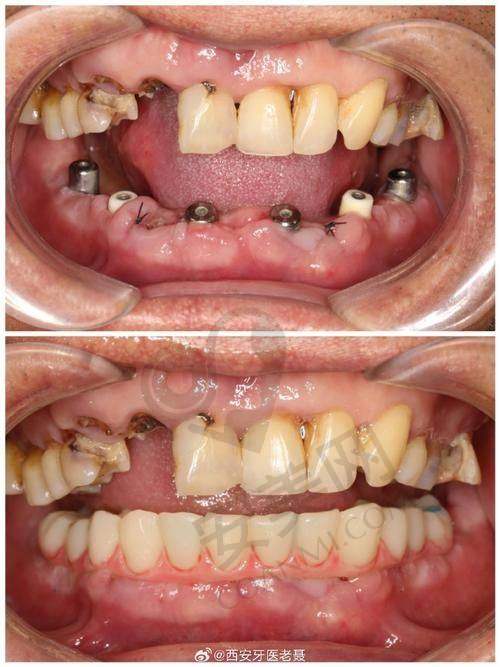

吕光彩医生是滨州牙博士口腔的核心骨干医生之一。他拥有丰富的临床经验,多年来专注于种植牙领域的研究和实践。在种植牙手术方面,他技术不错,手法细腻。每一台手术,他都会根据患者的具体情况,制定个性化的种植方案。他擅长处理各种复杂的口腔情况,比如牙槽骨条件不佳、多颗牙齿缺失等问题。许多患者在吕光彩医生的治疗下,成功地修复了牙齿功能,重拾了自信的笑容。他还不断学习和引进国内外精良的种植牙技术,让患者能够享受到更前列的口腔医疗服务。

首先,患者需要到医院进行初步的口腔检查。医生会使用精良的设备对患者的口腔进行全方面的扫描,了解牙槽骨的密度、高度、宽度等情况,以及是否存在其他口腔疾病。然后,医生会根据检查结果,为患者制定个性化的种植方案。如果患者对方案满意,就可以安排手术时间。在手术前,医生会对患者进行详细的术前指导,告知患者需要注意的事项。手术过程中,吕光彩医生会在局部麻醉的情况下,将种植体正确地植入牙槽骨内。手术后,患者需要按照医生的嘱咐进行护理和修复,定期到医院进行复查,直到种植体与牙槽骨完全结合,安装上合适的牙冠,整个种植牙过程才算完成。